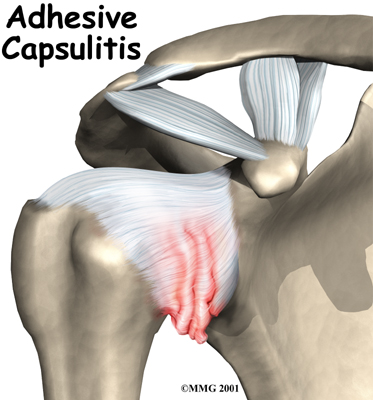

The shoulder is made up of three bones: the scapula (shoulder blade), the humerus (upper arm bone), and the clavicle (collarbone). The joint capsule is a watertight sac that encloses the joint and the fluids that bathe and lubricate it. The walls of the joint capsule are made up of ligaments. Ligaments are soft connective tissues that attach bones to bones. The joint capsule has a considerable amount of slack (loose tissue), so the shoulder is unrestricted as it moves through its large range of motion.

The shoulder is made up of three bones: the scapula (shoulder blade), the humerus (upper arm bone), and the clavicle (collarbone). The joint capsule is a watertight sac that encloses the joint and the fluids that bathe and lubricate it. The walls of the joint capsule are made up of ligaments. Ligaments are soft connective tissues that attach bones to bones. The joint capsule has a considerable amount of slack (loose tissue), so the shoulder is unrestricted as it moves through its large range of motion.

The terms frozen shoulder and adhesive capsulitis are often used interchangeably. In other words, the two terms describe the same painful, stiff condition of the shoulder no matter what causes it. A more accurate way to look at this is to refer to true adhesive capsulitis (affecting the joint capsule) as a primary adhesive capsulitis.

As the name suggests, adhesive capsulitis affects the fibrous ligaments that surround the shoulder forming the capsule. The condition referred to as a frozen shoulder usually doesn't involve the capsule. Secondary adhesive capsulitis (or true frozen shoulder) might have some joint capsule changes but the shoulder stiffness is really coming from something other than the joint capsule. Some of the conditions associated with secondary adhesive capsulitis include rotator cuff tears, biceps tendinitis, and arthritis. In either condition, the normally loose parts of the joint capsule stick together. This seriously limits the shoulder's ability to move, and causes the shoulder to relatively freeze.

As the name suggests, adhesive capsulitis affects the fibrous ligaments that surround the shoulder forming the capsule. The condition referred to as a frozen shoulder usually doesn't involve the capsule. Secondary adhesive capsulitis (or true frozen shoulder) might have some joint capsule changes but the shoulder stiffness is really coming from something other than the joint capsule. Some of the conditions associated with secondary adhesive capsulitis include rotator cuff tears, biceps tendinitis, and arthritis. In either condition, the normally loose parts of the joint capsule stick together. This seriously limits the shoulder's ability to move, and causes the shoulder to relatively freeze.

The shoulder is made up of three bones: the scapula (shoulder blade), the humerus (upper arm bone), and the clavicle (collarbone). The joint capsule is a watertight sac that encloses the joint and the fluids that bathe and lubricate it. The walls of the joint capsule are made up of ligaments. Ligaments are soft connective tissues that attach bones to bones. The joint capsule has a considerable amount of slack (loose tissue), so the shoulder is unrestricted as it moves through its large range of motion.

The shoulder is made up of three bones: the scapula (shoulder blade), the humerus (upper arm bone), and the clavicle (collarbone). The joint capsule is a watertight sac that encloses the joint and the fluids that bathe and lubricate it. The walls of the joint capsule are made up of ligaments. Ligaments are soft connective tissues that attach bones to bones. The joint capsule has a considerable amount of slack (loose tissue), so the shoulder is unrestricted as it moves through its large range of motion. As the name suggests, adhesive capsulitis affects the fibrous ligaments that surround the shoulder forming the capsule. The condition referred to as a frozen shoulder usually doesn't involve the capsule. Secondary adhesive capsulitis (or true frozen shoulder) might have some joint capsule changes but the shoulder stiffness is really coming from something other than the joint capsule. Some of the conditions associated with secondary adhesive capsulitis include rotator cuff tears, biceps tendinitis, and arthritis. In either condition, the normally loose parts of the joint capsule stick together. This seriously limits the shoulder's ability to move, and causes the shoulder to relatively freeze.

As the name suggests, adhesive capsulitis affects the fibrous ligaments that surround the shoulder forming the capsule. The condition referred to as a frozen shoulder usually doesn't involve the capsule. Secondary adhesive capsulitis (or true frozen shoulder) might have some joint capsule changes but the shoulder stiffness is really coming from something other than the joint capsule. Some of the conditions associated with secondary adhesive capsulitis include rotator cuff tears, biceps tendinitis, and arthritis. In either condition, the normally loose parts of the joint capsule stick together. This seriously limits the shoulder's ability to move, and causes the shoulder to relatively freeze.